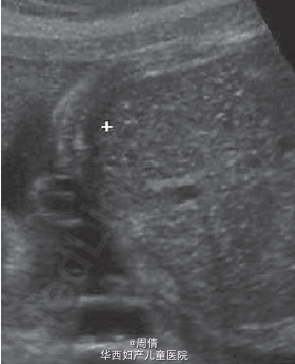

30岁女性,孕30+5周,因为12小时胎动减少入院

超声提示胎动减少,少量腹水,扩大的胆囊和扩张的小肠 多普勒提示胎盘缺氧,但和胎盘的血管没有关系 羊膜腔穿刺术提示羊膜内感染,G(+),糖减少,多核细胞增多